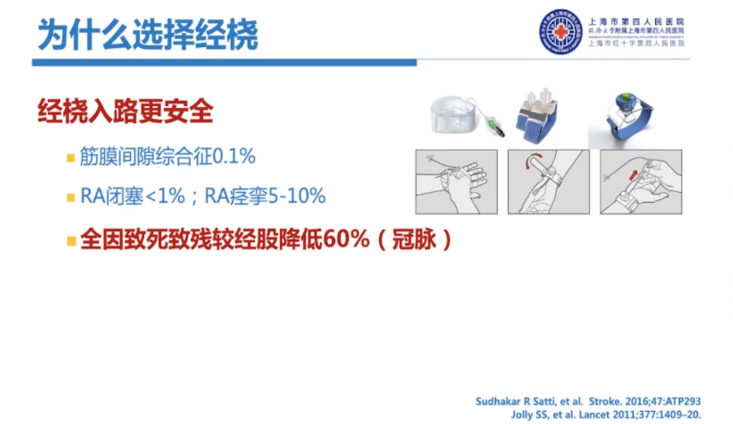

相较股动脉入路,经桡入路更安全,并发症发生率更低,筋膜间隙综合征为0.1%左右,RA闭塞<1%;RA痉挛5%-10%,全因致死、致残率较经股入路降低60%(冠脉),同时,对病人来说,术后舒适度更高,术后无需强制平卧(避免腰背疼痛、诱发心衰、下肢静脉血栓等),可即刻站立活动(更方便,自行如厕等)。